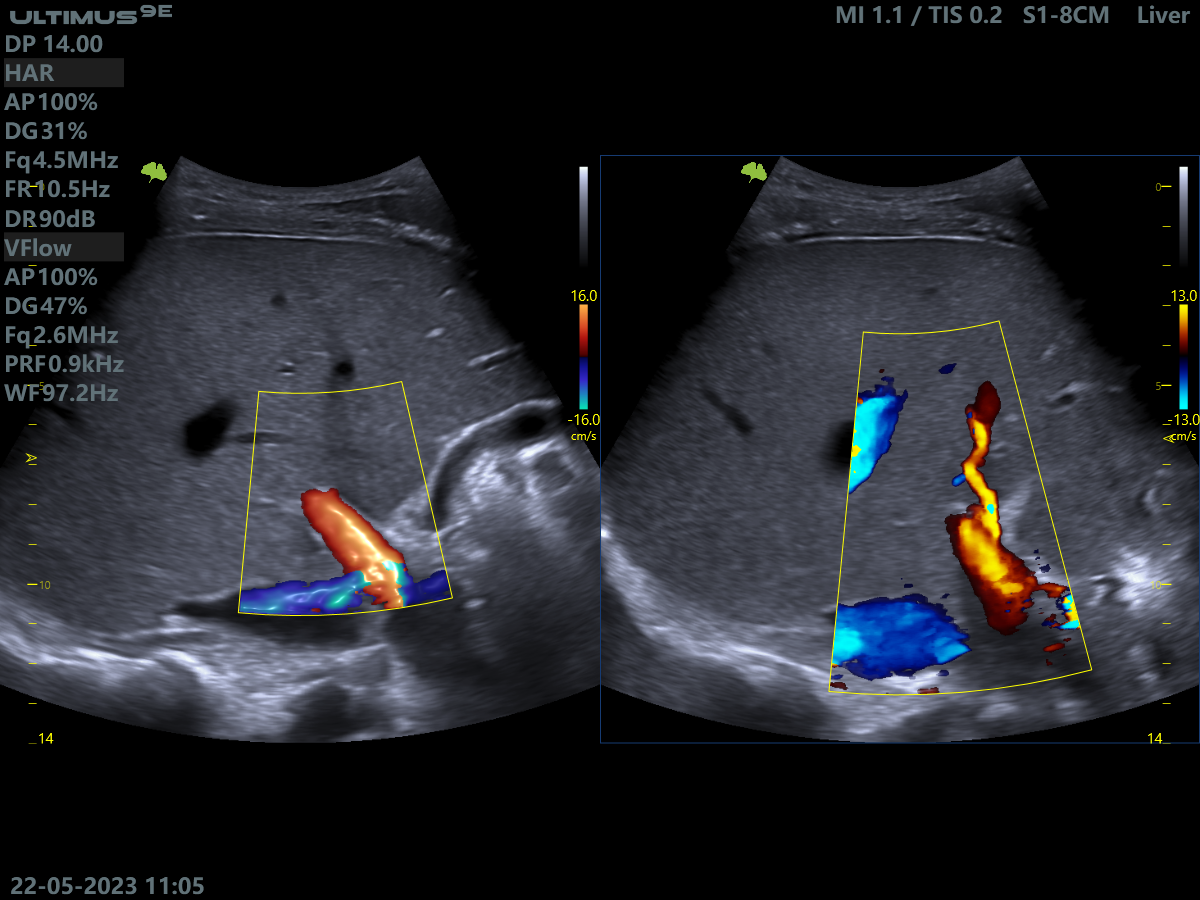

Клінічні зображення, що демонструють якість діагностики та можливості обладнання

Клінічне зображення 1

Клінічне зображення 2